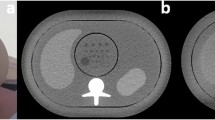

An anthropomorphic abdomen phantom (QRM 401) simulating three types of attenuations produced by an adult patient (Fig. 1) was used for this study. This phantom was called the small phantom (anterior posterior (AP) x lateral diameter: 20 x 30 cm) and represented a thin adult with a body mass index (BMI) of 20 kg/m2 or a patient weight of ~50 kg. To vary the patient’s morphology, two additional rings, one medium-sized (2.5 cm in thickness) and one large-sized (5 cm in thickness), were added to the phantom. With these two extra rings (AP x lateral diameter: 25 x 35 cm, and 30 x 40cm, respectively) the phantom represented patients with a BMI of 26 kg/m2 (patient weight ~90 kg) and 35 kg/m2 (patient weight ~120 kg), respectively. A cylindrical module containing spherical lesions 8, 6 and 5 mm in diameter with a contrast of 20 HU relative to the background at 120 kVp was inserted in the centre of the phantom (four spheres per diameter). It is worth mentioning the phantom is made of various plastics that do not contain any high atomic number materials. Thus, the variation of contrast with x-ray beam energy is negligible.